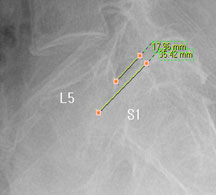

모커리한방병원 위 뼈가 50%정도 밀려나간 모습 이미지